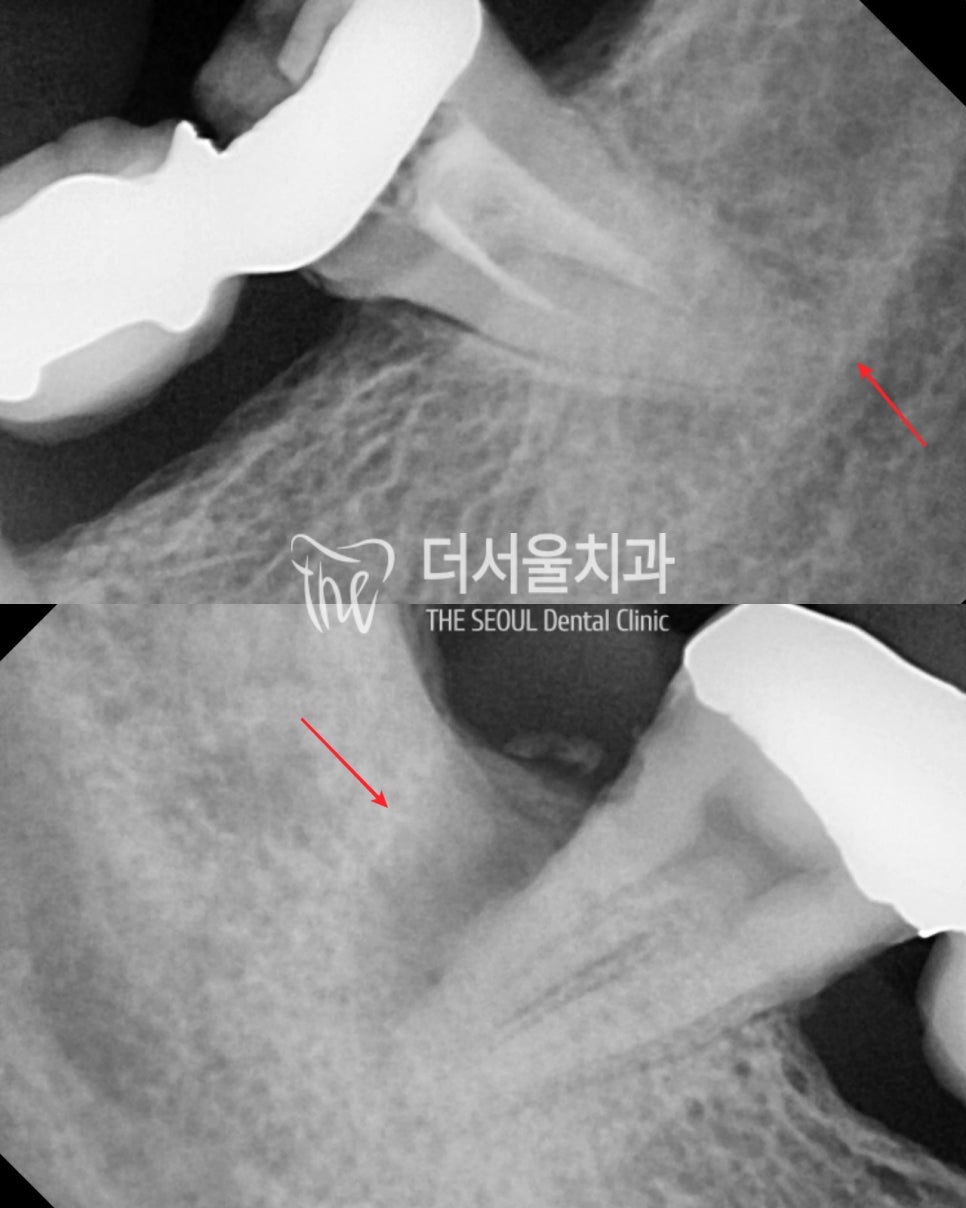

더 자세히 찍어봤습니다.

안 그래도 얼마 뿌리를 못 잡고 있는데

염증으로 좋지 않은 상황입니다.

이 상태를 더 방치했다가

남아있던 치조골도 더 흡수되어서

임플란트 치료도 받기 힘들어 질 수도 있습니다.